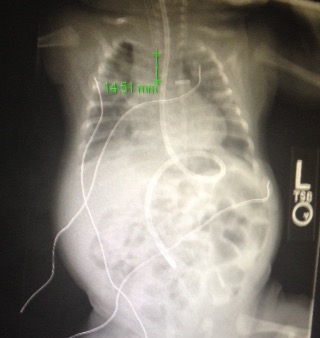

They had an xray this morning that looks quite good for RT!

She feels like we can go slightly faster because his xray looks so good, not sure how I feel about going that quick, now that I have accepted we will go slow.